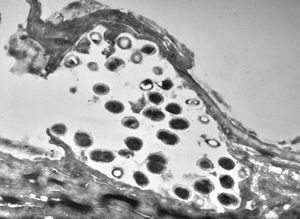

F, 24y. | molluscum contagiosum … virions

F, 24y. | molluscum contagiosum

F, 24y. | molluscum contagiosum

F, 7y. | molluscum contagiosum … virions

F, 7y. | molluscum contagiosum … virions

F, 24y. | molluscum contagiosum … virions